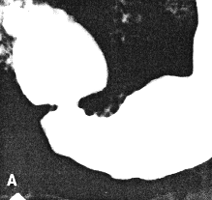

Case 37.1. D.R., 40 year old male had a long history of ethanol abuse and insulin- dependent diabetes mellitus which had been treated inadequately. For several weeks there had been dyspepsia, loss of appetite and nausea. Radiologically primary and secondary oesophageal peristaltic waves were normal. After an overnight fast the stomach contained food residues; the pyloric aperture was patent, measuring 9.0. mm in diameter (Fig. 37.1A). Gastric peristaltic waves were decreased both in frequency (i.e. less than 3 per minute) and intensity (i.e. failing to "bi-sect" the organ). The pyloric sphincteric cylinder was in a state of partial contraction most of the time (Fig. 37.1B). Cyclical contraction and relaxation of the cylinder, normally occurring at a frequency of 3 per minute (Chaps. 13, 15), was lacking. No obstructing lesion was seen at the pylorus and the duodenum appeared normal. Sonographically the gall bladder, liver, spleen and kidneys were normal; there was no ascites. The patient refused endoscopic examination.

| Fig. 37.1. A,B. Case D.R. A Food residues in stomach. Pyloric aperture patent. Gastric peristaltic activity diminished. B Pyloric sphincteric cylinder (arrows) contracted most of the time. |

Six months later, after proper diabetic control, he had improved clinically. On this occasion the stomach contained less residual food. Shallow gastric peristaltic waves were present, while the pyloric sphincteric cylinder remained partially contracted throughout the examination (Fig. 37.1C). Although this was less marked than on the previous occasion, normal cyclical activity remained absent and no maximal or complete contractions were seen. Peristaltic activity in the duodenum appeared to be decreased. Active peristaltic contractions with a fast passage of barium was noted in the jejunum. The films also showed scattered areas of calcification in the pancreas and the case was diagnosed as diabetic gastroparesis and chronic alcoholic pancreatitis. Case 37.2. T.M., 64 year old female with longstanding insulin-dependent diabetes mellitus and psychotic symptoms, was admitted with epigastric pain and episodes of vomiting. Radiological examination showed a decrease in frequency and intensity of gastric peristaltic waves; there was a lack of cyclical contraction and relaxation of the pyloric sphincteric cylinder, which remained in a state of partial contraction throughout the examination; this was associated with a patulous pyloric orifice measuring 1.2 cm in diameter. Sonographically the gall bladder, liver, spleen, kidneys and aorta were normal. The pancreas could not be visualized owing to obesity.